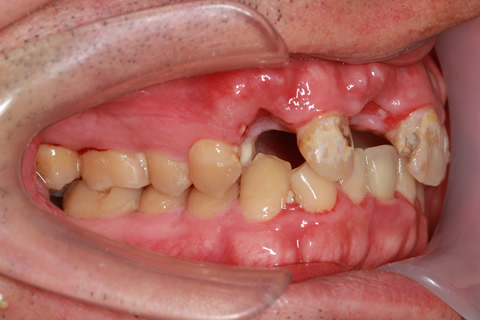

症例4

- 年齢・性別

- 60歳

- 治療期間

- 6ヶ月

- 抜歯

- 残根抜歯のみ

- 治療費

- 198万円

- 備考

- 右上5.6 右下5 左下4.5.6欠損

- 治療内容

- 6本のインプラントを右左側に2回に分けて埋入

- 施術の副作用(リスク)

- オペによる知覚障害。インプラントによる歯肉炎。インプラント脱落。